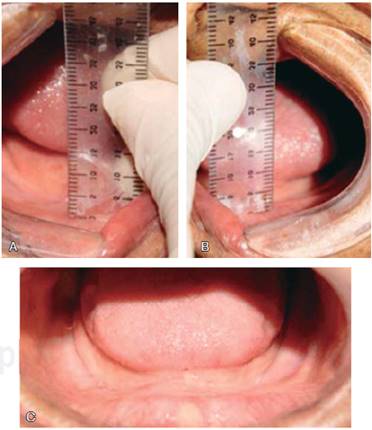

Se llevó a cabo un ensayo clínico cruzado (con el sujeto como su propio control). Se realizó un muestreo de conveniencia seleccionando a los sujetos de la Clínica de Prostodoncia Total de la Facultad de Odontología, UNAM, totalmente desdentados con una clasificación del reborde residual V o VI según Cawood y Howell (1988), con una altura no mayor a 2 mm, en un rango de edad de 55 a 85 años, sin patologías mentales y controlados sistémicamente (Figuras 1 y 2). Fueron evaluados inicialmente apreciando la actitud mental House Boucher.2 A todos los pacientes seleccionados se les invitó a participar en la investigación, los sujetos que aceptaron lo realizaron bajo consentimiento válidamente informado. Se realizó el procedimiento clínico, dividiendo en dos grupos a los sujetos. El grupo 1 fue designado a utilizar inicialmente las PC, el grupo 2 a utilizar inicialmente las PG. Para ambos se estableció un periodo de uso de seis meses, realizando los ajustes requeridos, así como dando indicaciones por escrito. Después se duplicaron las prótesis inferiores impresionando a boca cerrada, para después cambiar de grupo (diseño cruzado) (Figura 3).

Figura 2 Clase V del reborde residual. A y B) 2 mm de altura del reborde residual zona de premolares derecho e izquierdo respectivamente. C) Características clínicas requeridas para la inclusión en el estudio.